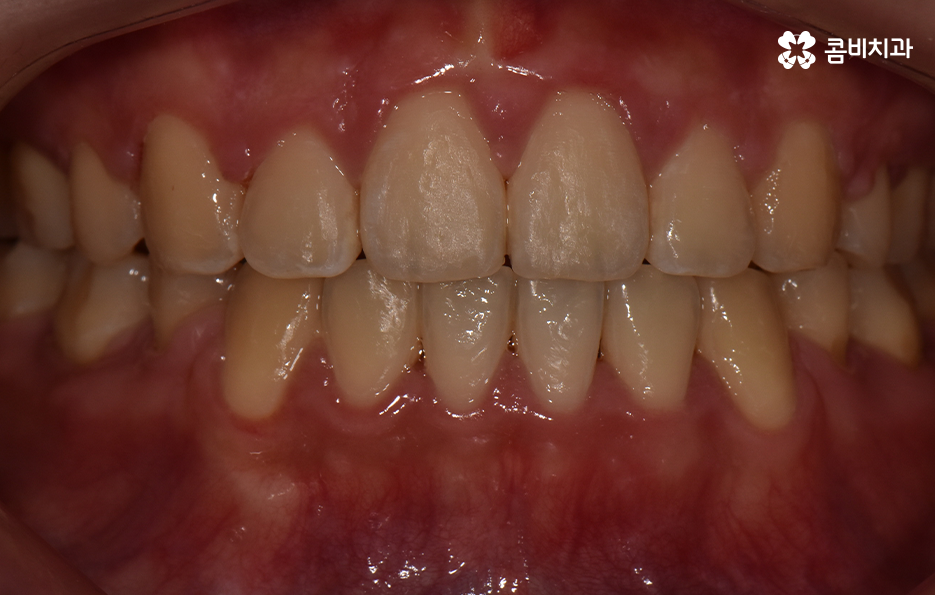

이처럼 치열의 변화는 얼굴형 변화에도 많은 영향을 줄 수 있기 때문에 치아교정의 만족도는 치열뿐 아니라 환자 개개인의 골격과 얼굴형을 고려하여 잘 어울리는 조화적인 측면과 치아의 건강 등 고려해야 할 점이 많다는 것을 알 수 있는데요

오늘은 돌출입발치교정 통해서 치열도 가지런하게 교정하고 얼굴형의 변화뿐 아니라 교합까지 잘 맞물려서 건강하게 치아교정을 하는 방법에 대해 알아볼 거예요

치아를 발치하고 이동하면서 얼굴 변화의 대표적 사례는 돌출입 개선이나 얼굴 라인의 변화뿐 아니라 얼굴 비대칭의 개선이나 팔자주름이 옅어지는 등의 변화를 꼽을 수 있어요